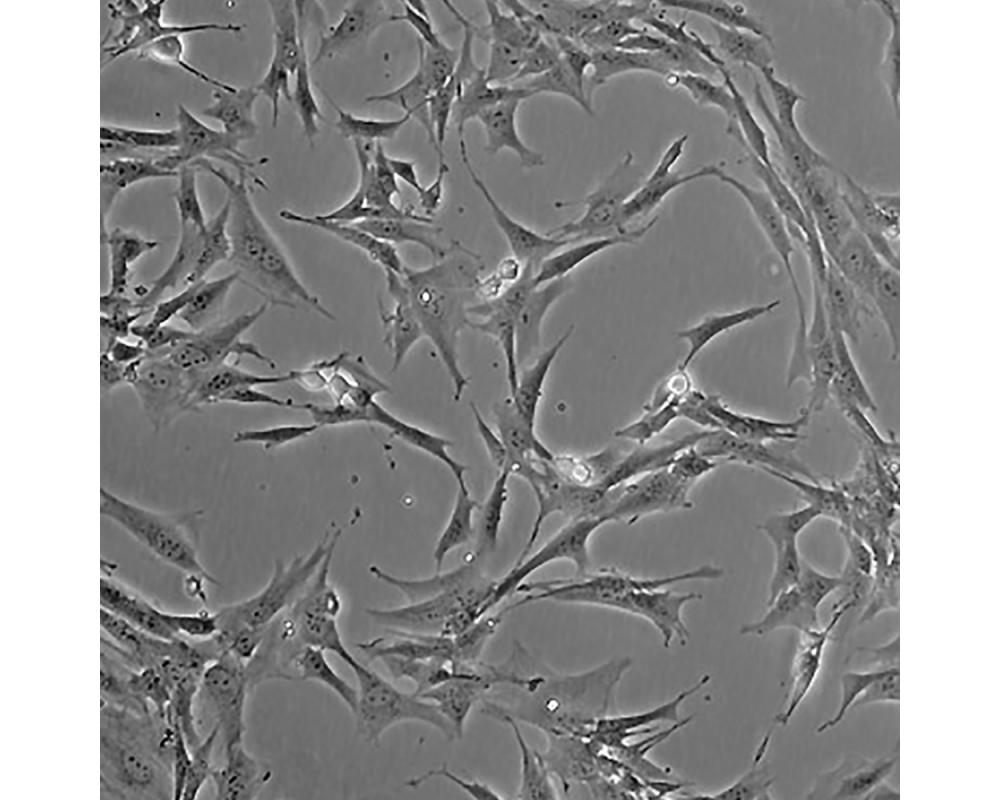

產(chǎn)品名稱 BHK-21

中文名稱 倉鼠腎成纖維細(xì)胞

形態(tài)特征 成纖維細(xì)胞樣

生長特性 貼壁生長

特征特性 該細(xì)胞系是于1961年由Macpherson IA、Stoker MGP建系,源自5只未辨性別的1天齡倉鼠腎;可作為轉(zhuǎn)化宿主;OIE組織將該細(xì)胞用于狂犬病的診斷。

培養(yǎng)條件 DMEM(高糖)+10%FBS(gibco)

傳代方法 1:2傳代,每周換液1~2次。